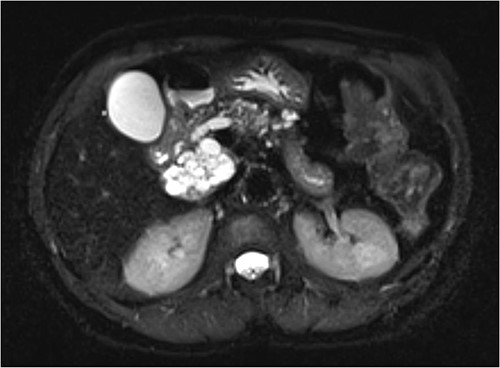

Magnetic resonance imaging (MRI) revealed a 6.9 cm multi-lobulated cystic pancreatic head lesion with underlying background changes of alcohol-related chronic pancreatitis. There was no biliary or pancreatic duct dilation, or other suspicious features for malignancy (Fig. 1). This lesion was thought to be a serous cystadenoma or pancreatic pseudocyst. Endoscopic ultrasound (EUS) revealed innumerable small cysts consistent with serous cystadenoma and fine-needle biopsy demonstrated benign ductal epithelium.

Multi-loculated head of pancreas cyst, with no pancreatic duct dilation.